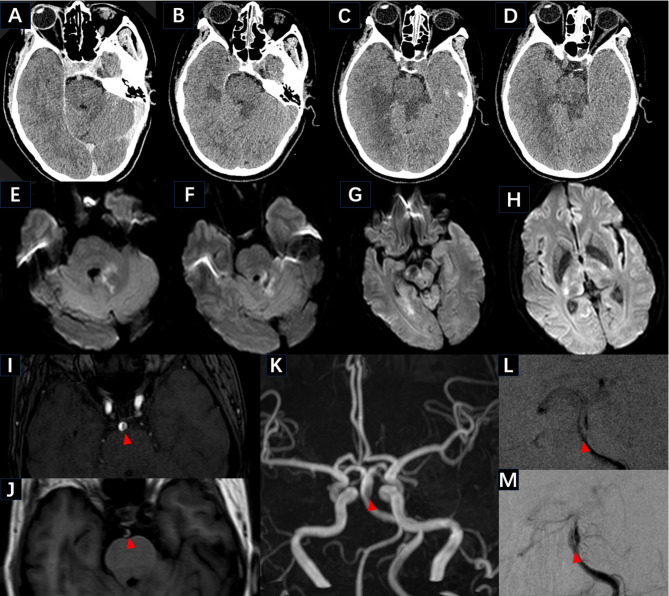

背景:静脉溶栓(IVT)治疗急性缺血性脑卒中(AIS)合并颅内动脉夹层(IAD)的临床疗效尚不确定。本研究报告一例基底动脉夹层(BAD),患者为57岁的亚洲女性,既往无卒中危险因素,但突然出现意识障碍。患者的临床状况在静脉注射期间恶化,但随后的医疗干预和康复锻炼促进了日常功能的最终恢复。MRI最终确定了患者AIS的病因。结论:AIS与前循环IAD相关,在IVT早期可能存在较高的出血转化和症状加重风险,但对远期预后的影响尚不确定。因此,有必要进一步研究IVT在此类患者中的安全性和有效性。

Background: The clinical efficacy of intravenous thrombolysis (IVT) for acute ischemic stroke (AIS) associated with intracranial artery dissection (IAD) remains uncertain. This study presents a case of basilar artery dissection (BAD) in a 57-year-old Asian female patient devoid of previous risk factors for stroke who experienced a sudden onset of consciousness disturbance. The patient's clinical condition deteriorated during IVT administration, but subsequent medical intervention and rehabilitative exercises facilitated eventual recovery of daily functioning. MRI eventually identified the etiology of the patient's AIS.

Conclusion: AIS related to anterior circulation IAD may pose a relatively high risk of hemorrhagic transformation and symptom exacerbation during the early stages of IVT, but the impact on long-term prognosis remains uncertain. Consequently, further investigation is warranted to assess the safety and efficacy of IVT in such patients.